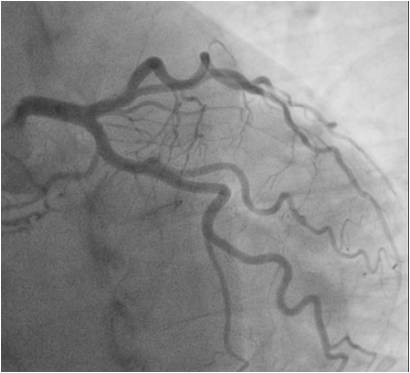

Taking into account the age of the patient, the nature of the underlying and concomitant pathology, the results of laboratory and instrumental research methods, it was decided that it would be expedient to perform selective coronary angiography as part of the preoperative additional examination. According to the latter, no hemodynamically significant stenoses of the coronary arteries were found (Figure 4). As an artifact, a branch of the left coronary artery was found, which forms 2 bronchial arteries of the right lung (Figure 5).

Fig. 4. Angiography results: no hemodynamically significant stenoses were found.